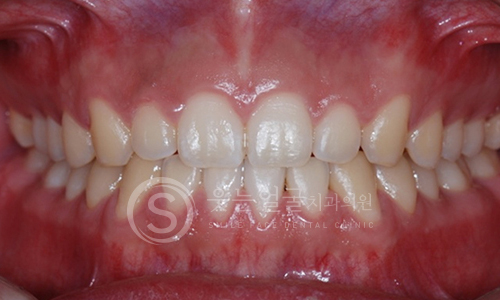

한눈에 보는

치아교정 전후사진